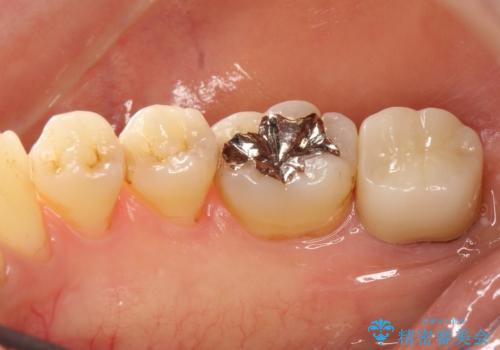

[フルジルコニアクラウン] 老朽化した銀歯を白く